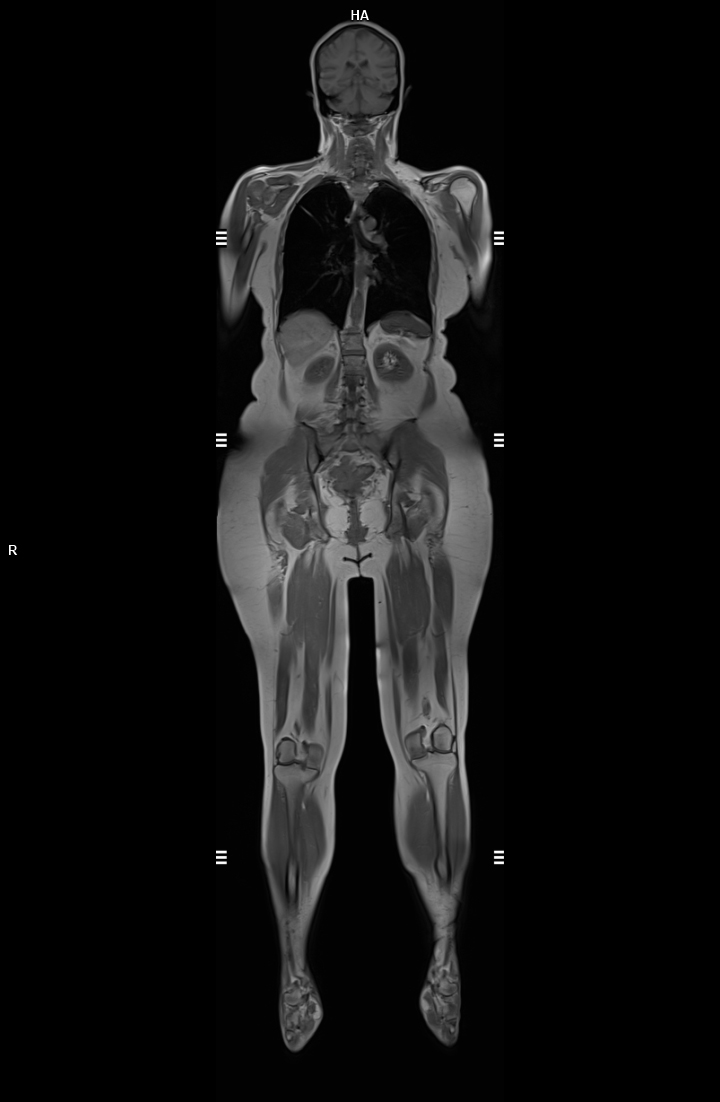

Tüm Vucut MR

1. Yüksek Görüntü Kalitesi

Detaylı Görüntüleme: 3 Tesla manyetik alan, daha yüksek çözünürlükte ve detaylı görüntüler sağlar. Küçük anatomik yapılar ve patolojiler daha net bir şekilde görüntülenebilir.

Keskin Kontrast: Yumuşak doku kontrastı daha belirgindir, bu da kanser, tümör gibi hastalıkların tespitinde önemlidir.

Onkolojik İncelemeler: Kanserli dokuların tespitinde ve evrelemesinde daha etkili sonuçlar verir.

Kompleks vakaların (örneğin beyin tümörleri, kalp anomalileri) değerlendirilmesinde tercih edilir.